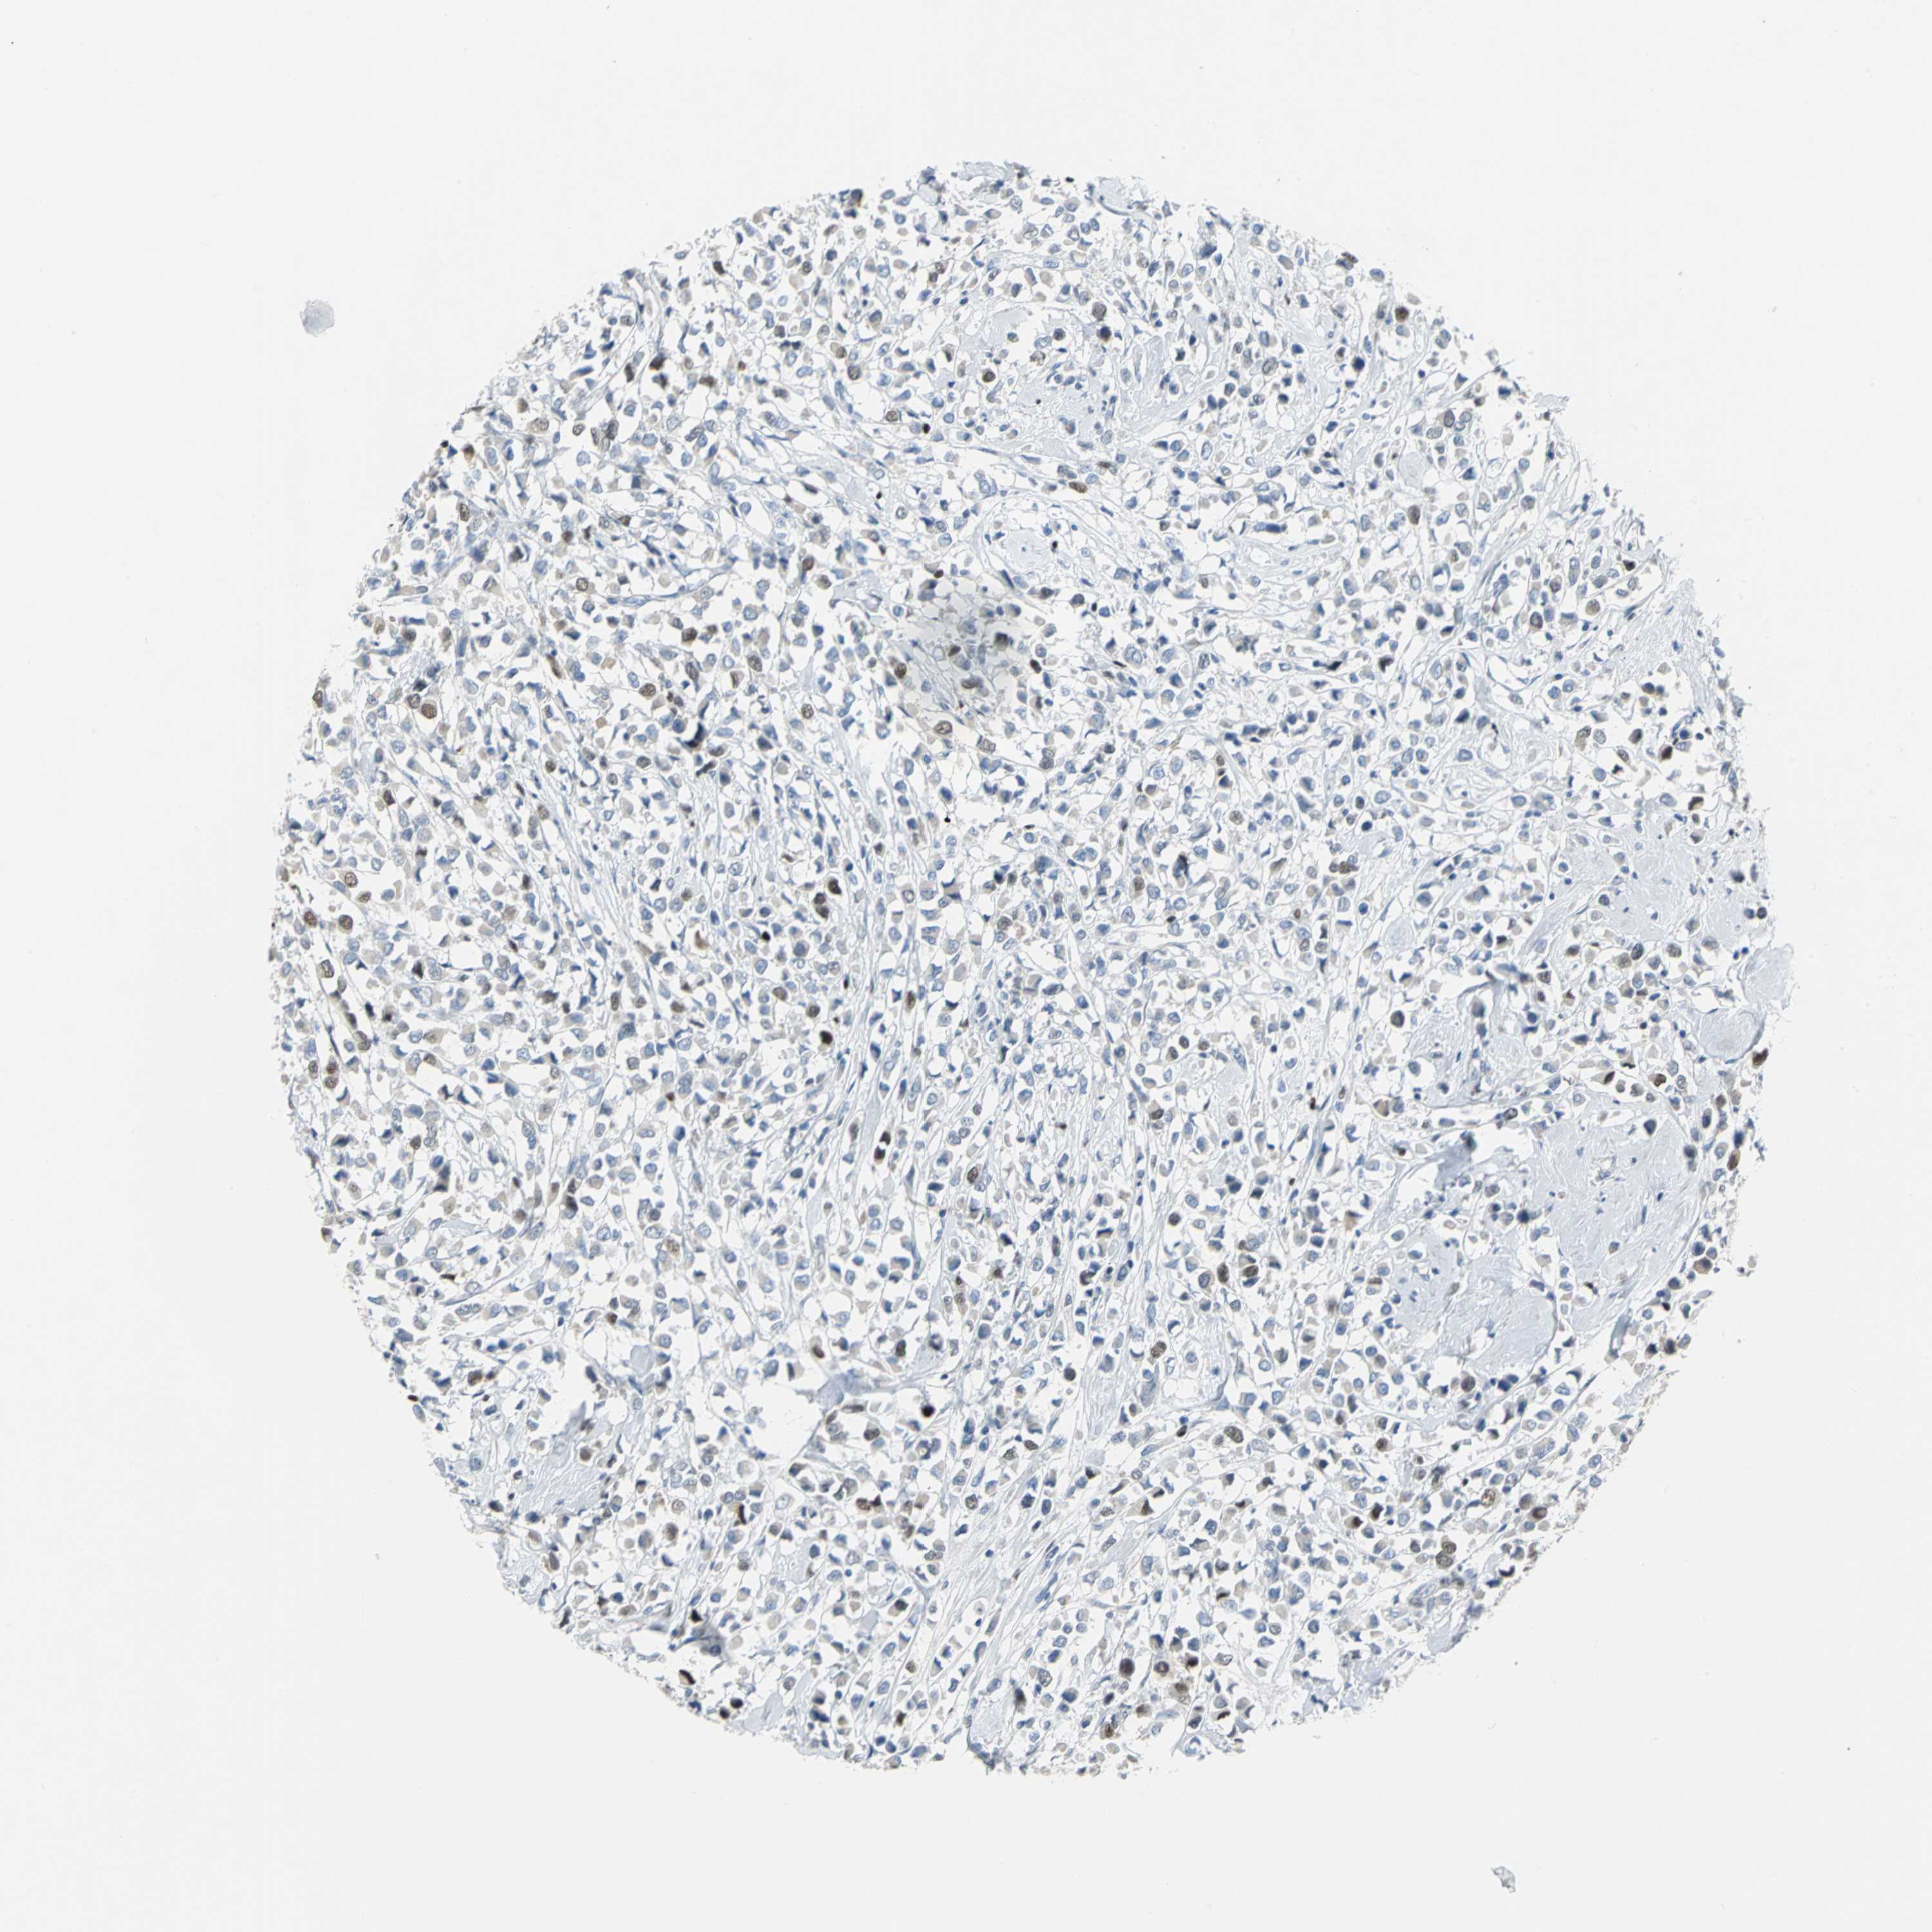

BRCA TCGA BRCA VALIDATION PROTEIN EXPRESSION